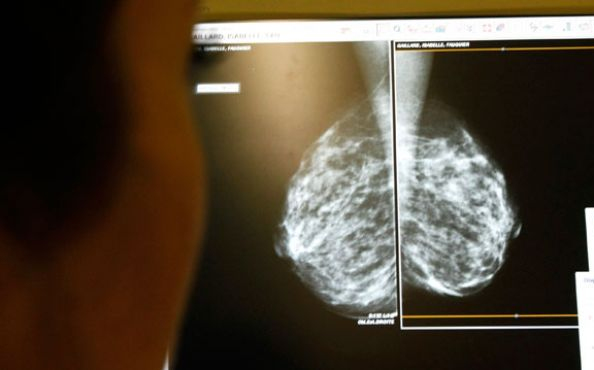

3D mammográfiával könnyebben felismerhető a mellrák

Bár a hagyományos mammográfia a legelterjedtebb eszköz a mellrák szűrésére, a Pennsylvania Egyetem kutatóinak tanulmánya szerint a digitális mell tomoszintézis, vagy más néven 3D-s mammográfia hatékonyabban képes felismerni a betegséget - írja a Fox News.

A tanulmány szerint a 3D mammográfia jóval pontosabb képet ad az orvosok számára, így kevesebb tévesen pozitív diagnosztika születik. A kutatás keretében mintegy 15 ezer nő 3D-s mammográfiájának eredményét vették szemügyre és hasonlították azt össze mintegy 10 ezer nőével, akik a hagyományos mammográfia vizsgálaton vettek részt.

Összességében megállapították, hogy a 3D-s mammográfia csökkenti a tévesen pozitív eredményeket, így kevesebb páciensnek kell visszamennie további vizsgálatokra.